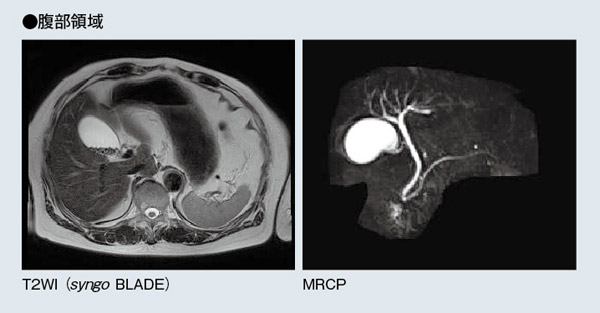

同クリニックではいまのところ,頭頸部領域と整形領域の撮像が約8割を占めている。頭頸部領域では,出血を疑う症例や外傷以外は基本的にMRIがファーストチョイスとなり,症例は脳梗塞や脳動脈瘤,一過性脳虚血発作(TIA)などが多い。MAGNETOM Avanto1台体制では,アキシャルのT2強調像,T2 FLAIR,T1強調像,拡散強調画像(DWI)を基本としていたが,MAGNETOM ESSENZAは検査スループットが高いため,同じ撮像時間でT2*強調像のほか,必要に応じてSWIまで追加できるようになった。また,整形領域では,腰椎椎間板ヘルニアや脊柱管狭窄症,半月板損傷,靭帯損傷などの撮像が多く行われている。腰椎では,T2強調像,T1強調像が2方向ずつに加えて,MRミエログラフィが追加された。このほか,腹部領域では,胆石の術前MRCP,T2強調像,T1強調像,DWIに加えて,3DのT1強調ダイナミックMRIであるsyngo VIBEを撮像している。息止め下約20秒で三次元画像が得られ,病変部の細かい部分まで容易に観察できるため,有用性が高いという。

腹部領域においては,呼吸をはじめとした体動の補正に優れているため,ルーチン検査でsyngo BLADEを用いている。

MRCPも,MAGNETOM Avantoと同等の画質が得られている。